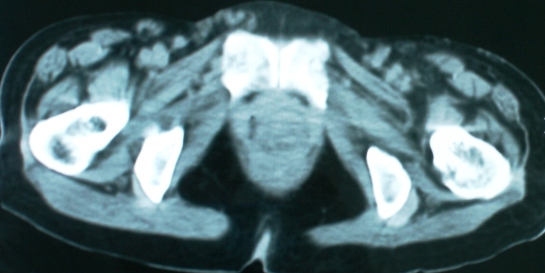

以下是引用zsl6918在2008-11-4 19:14:00的发言:[br]多发转移性改变,子宫改变不除外为原发灶